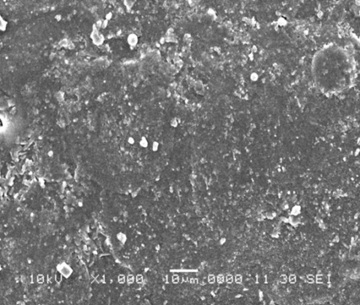

Abstract: The present study deals with the formulation of two-compartment capsule consisted of immediate release powder formulation of domperidone in the cap portion, polymer film fixed on the capsule body horizontally to create two compartments and omeprazole enteric pellets exhibiting a lag time, in the body portion. Domperidone and omeprazole, used in the treatment of gastro-esophageal reflux disease were selected as model drugs. Polymer film acted as dividing wall was made of HPMC and ethyl cellulose. It was assessed for uniformity of weight, thickness, folding endurance and tensile strength. Surface characteristic of film by scanning electron microscopy showed no cracks or pores. Evaluation tests of two-compartment capsule showed no transfer of drug in between two compartments through the polymer film. The results showed the capability of achieving two-compartment capsular system to handle varying release of solid-solid drugs in a single dosage form.

Fig : Scanning Electron Microscopy of polymer Film.